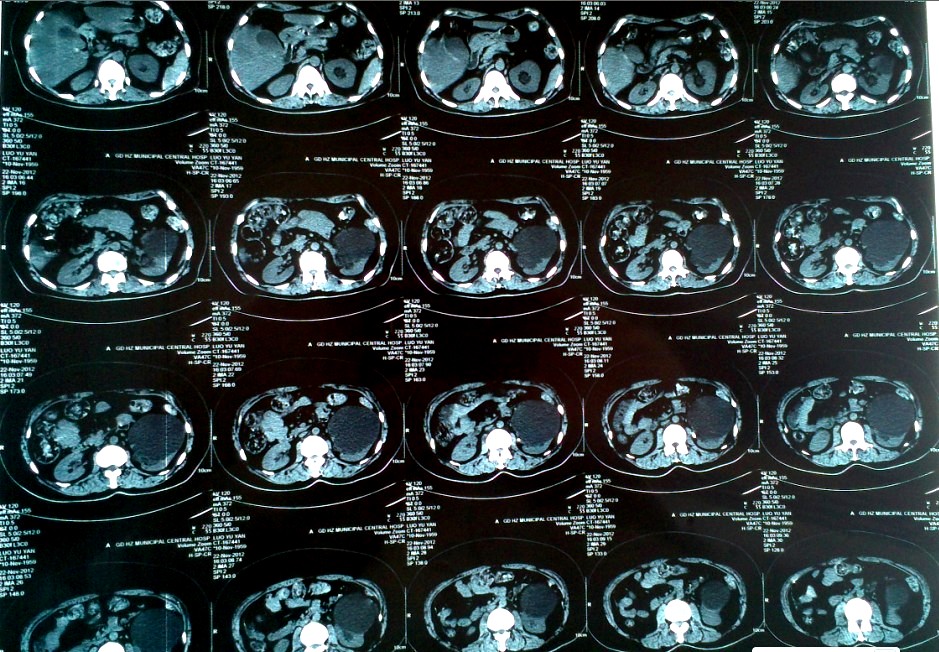

图片 CT片显示左肾囊肿位于肾中极紧贴并挤压腹腔

患者骆某,女性,53岁,因“左侧腰腹部疼痛10天余”来我院。就诊之前曾在多家大型综合医院就诊,均诊断为“左肾巨大囊肿,左输尿管上段结石并左肾积水”,按照一般治疗原则,行腹腔镜手术很容易就可以将肾下极的囊肿摘除,是治疗肾囊肿的首选术式。但是该患者囊肿的位置偏偏不在肾下极而且紧贴腹腔,加上合并输尿管结石、肾积水无疑给手术操作带来了极大的难度及迷惑性,所以几家大医院均建议开放手术,患者及家属对于开刀手术极不赞同,为此抱着试试看的态度来到我院。

我院自2007年以来在本地区率先开展各类泌尿腹腔镜手术至今已超过300例,其中包括一大批更复杂更难做的复杂性手术我们均顺利完成,积累了一定的经验,已经掌握了较为娴熟的操作技巧,所以,当泌尿外科杨伟忠主任在仔细询问病史、阅过CT和肾静脉造影片后斩钉截铁的对患者及家属说:“放心,我们可以微创手术帮你解决,不用开刀!”

20121128920分在手术室全麻下先利用输尿管镜为患者解除了左侧输尿管结石及肾积水,然后利用三个“小洞”的腹腔镜手术将复杂而又迷惑的肾囊肿彻底切除。为什么说是迷惑的肾囊肿呢?因为患者左输尿管上段结石合并了肾积水,很有可能是肾盏憩室,那么假如判断失误将肾盏憩室或积水肾皮质切除掉,后果可就不堪设想了,瘘尿、腹膜后感染等并发症就会接踵而至。可喜的是术后病理结果证实就是肾囊肿。